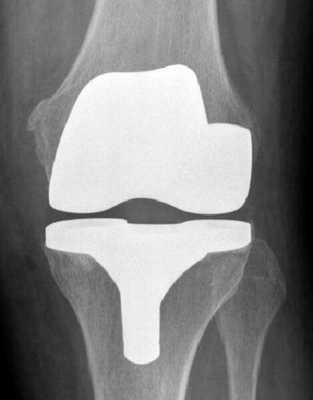

Проведение эндопротезирования считается крайней мерой, назначаемой при невозможности восстановления коленного сустава другими способами. Операцию выполняют чаще всего при артрите, артрозе, серьезных травмах.

Операция по замене коленного сустава является одним из вариантов лечения коленного сустава, поврежденного остеоартритом. Остеоартроз развивается вследствие разрушения суставного хряща и подлежащей кости.

Во время процедуры хирург удалит поврежденный хрящ и кость перед имплантацией искусственного сустава, содержащего металл, пластик и другие синтетические материалы.

Ежегодно в России проводится более 100 тысяч таких операций. Во время процедуры хирург удаляет коленный сустав и заменяет его металлическим, керамическим или пластиковым. Нужно сказать, что сейчас сделать эндопротезирование коленного сустава несложно, и квоты на это государство охотно выделяет.

Рентген после операции. Протез стоит корректно.